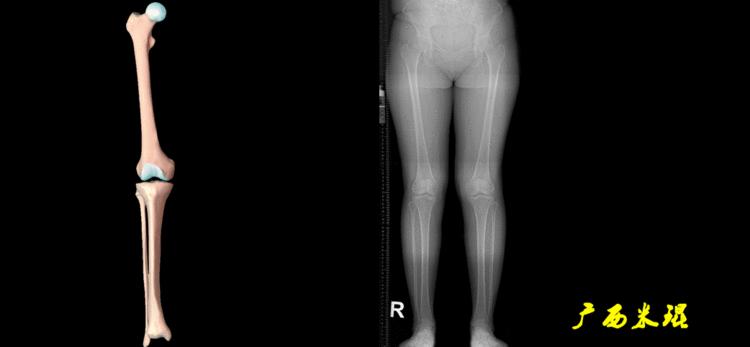

下肢力线及相关角度测量是骨科医生必须要掌握的基础知识,临床上关节疼痛的诊断、截骨矫形和关节置换手术前后等都需要用到这方面的知识,脑海中还没有这方面的概念就去给病人诊断甚至手术治疗,后果是可怕的。刚开始的时候可能感觉这些东西很难,其实只要掌握要点,反复实践,就很快能够熟练的使用它。

下肢力线及相关角度测量的前提是必须拍摄标准的站立位也就是负重位的下肢全长片。目前这样的照片都是放射科的技师在电脑上拼接出来的,大部分医院的DR都能够做到这一点。

无论如何,拍摄出来的下肢全长片必须包含髋关节中心、膝关节中心及踝关节中心,否则对临床是无用的。有了一张下肢的全长照片,我们需要确定下肢关节的中心点,通过中心点画出下肢的各种轴线,然后利用轴线与关节线的相交得出各种所需要的角度。

2、画出下肢的轴线

确定髋关节、膝关节、踝关节的中心点后,我们才能了解下肢的几个轴线。

(2)机械轴

机械轴是连接近端和远端关节中心点的直线。

机械轴要分前后位及侧位,站立前后位(也就是冠状面)股骨头中心与踝关节中心的连线通过膝关节中心,这是下肢的机械轴线,也就是下肢力线,常说Mikulicz线。冠状面的力线评估在临床工作中最常用、最基础、最重要。